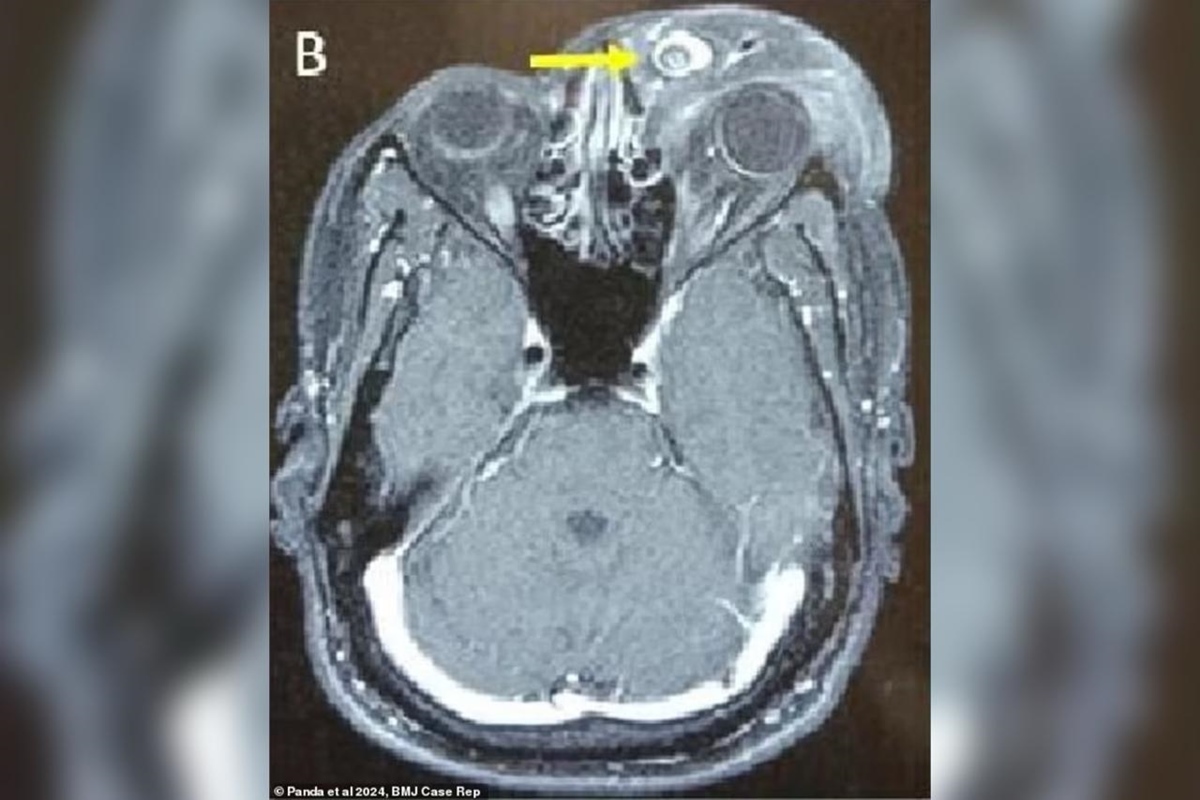

Um caso raro da doença foi registrado na Índia e detalhado na revista científica BMJ Case Reports no dia 17 de outubro. Um homem indiano de 30 anos ficou cego e sofreu deformações faciais após o parasita se alojar em seu globo ocular.

O problema teve início há cinco anos, quando o paciente notou um leve inchaço no olho esquerdo. Com o passar do tempo, o tumor se desenvolveu, esticando a pele do rosto e comprometendo a estrutura ocular, até que ele perdeu completamente a visão. O homem ficou com uma espécie de bolsa de pele que saía do olho e ficava pendurada no rosto.

O tumor, que tinha 15 centímetros de diâmetro e estava preso a uma bolsa de tecido ocular de 7,5 centímetros de comprimento, não era cancerígeno, mas ainda assim causava efeitos colaterais debilitantes.